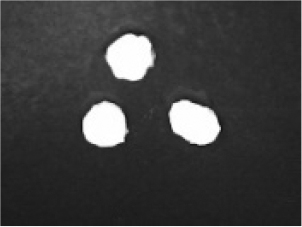

In addition to the disintegration endpoint studied using the USP disintegration apparatus, the pellets disintegrated into particles of various sizes when evaluated at a static position. A few drops of water were placed on the pellets on the opaque surface. A USB digital microscope (China) was connected to a computer to capture the disintegration process. Images were captured from the beginning until the pellet disintegrated or exploded into small fragments. Pellet images were acquired every 30 seconds. for formulations containing polyplasdone XL 10 and croscarmellose sodium.

Disintegration was evaluated at room temperature under static conditions. The camera captured images every 30 s ( Table 9), illustrating that MCC pellet X3 with mannitol and PEG 400 did not disintegrate. Within 120 s, cracks appeared in P5 pellets containing mannitol, PEG, and PPXL. As seen in the C4 pellets, they begin to explode into many fragments within 30 s. Moreover, the CP12 pellets containing PEG 400, mannitol, CCS, and PPXL began to explode into many loosely linked particles after 60 s, which quickly separated under the oscillating motion of the USP disintegration equipment. The photographs are compatible with the results mentioned above for the USP disintegration device. When the temperature was increased to 37°C, the disintegration caused the split into tiny fragments.

Table 9. Camera capture of pellet disintegration at different time intervals.

Pellet # 0 sec. 30 sec. 60 sec. 90 sec. 120 sec.

X3c9c3975f-9288-4951-a800-a8e9fc463382_GRA58.gif c9c3975f-9288-4951-a800-a8e9fc463382_GRA59.gif c9c3975f-9288-4951-a800-a8e9fc463382_GRA60.gif c9c3975f-9288-4951-a800-a8e9fc463382_GRA61.gif c9c3975f-9288-4951-a800-a8e9fc463382_GRA62.gif

P5c9c3975f-9288-4951-a800-a8e9fc463382_GRA63.gif c9c3975f-9288-4951-a800-a8e9fc463382_GRA64.gif c9c3975f-9288-4951-a800-a8e9fc463382_GRA65.gif c9c3975f-9288-4951-a800-a8e9fc463382_GRA66.gif c9c3975f-9288-4951-a800-a8e9fc463382_GRA67.gif

C4c9c3975f-9288-4951-a800-a8e9fc463382_GRA68.gif c9c3975f-9288-4951-a800-a8e9fc463382_GRA69.gif c9c3975f-9288-4951-a800-a8e9fc463382_GRA70.gif c9c3975f-9288-4951-a800-a8e9fc463382_GRA71.gif c9c3975f-9288-4951-a800-a8e9fc463382_GRA72.gif